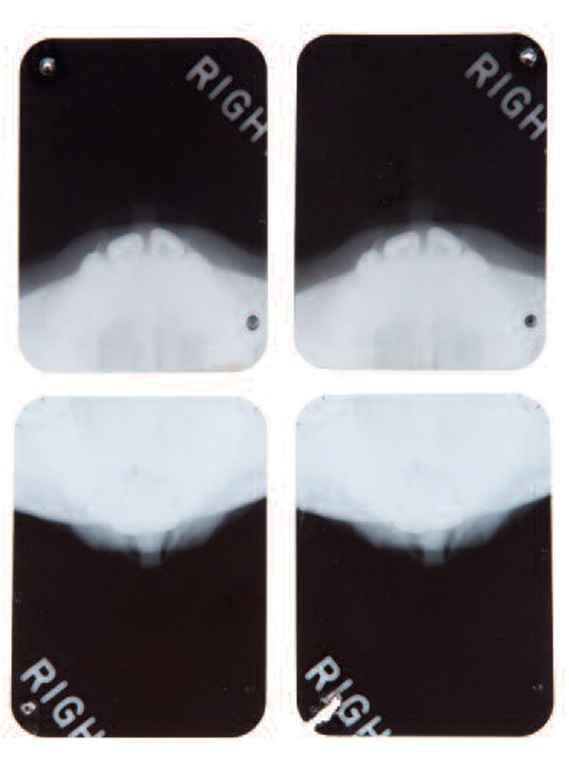

Il pettegolezzo sul ricorso al bisturi sembra infatti trovare conferma dagli appunti di un medico, il defunto dott. Michael Gurdin. Una sorta di ‘cartella sanitaria’ dell’attrice, con tanto di lastre, in cui si fa riferimento ad un intervento estetico al mento e ad una rinoplastica effettuata nel 1950.

I raggi X sono invece del 7 giugno 1962, due mesi prima della sua morte, avvenuta all’eta’ di 36 anni per un’overdose di barbiturici. Le lastre al cranio, alle ossa nasali e al palato, insieme alla documentazione sanitaria della star americana, saranno messe all’asta a Beverly Hills, in California, il prossimo 9 novembre. La base di partenza e’ tra i 15 e i 20 mila dollari.